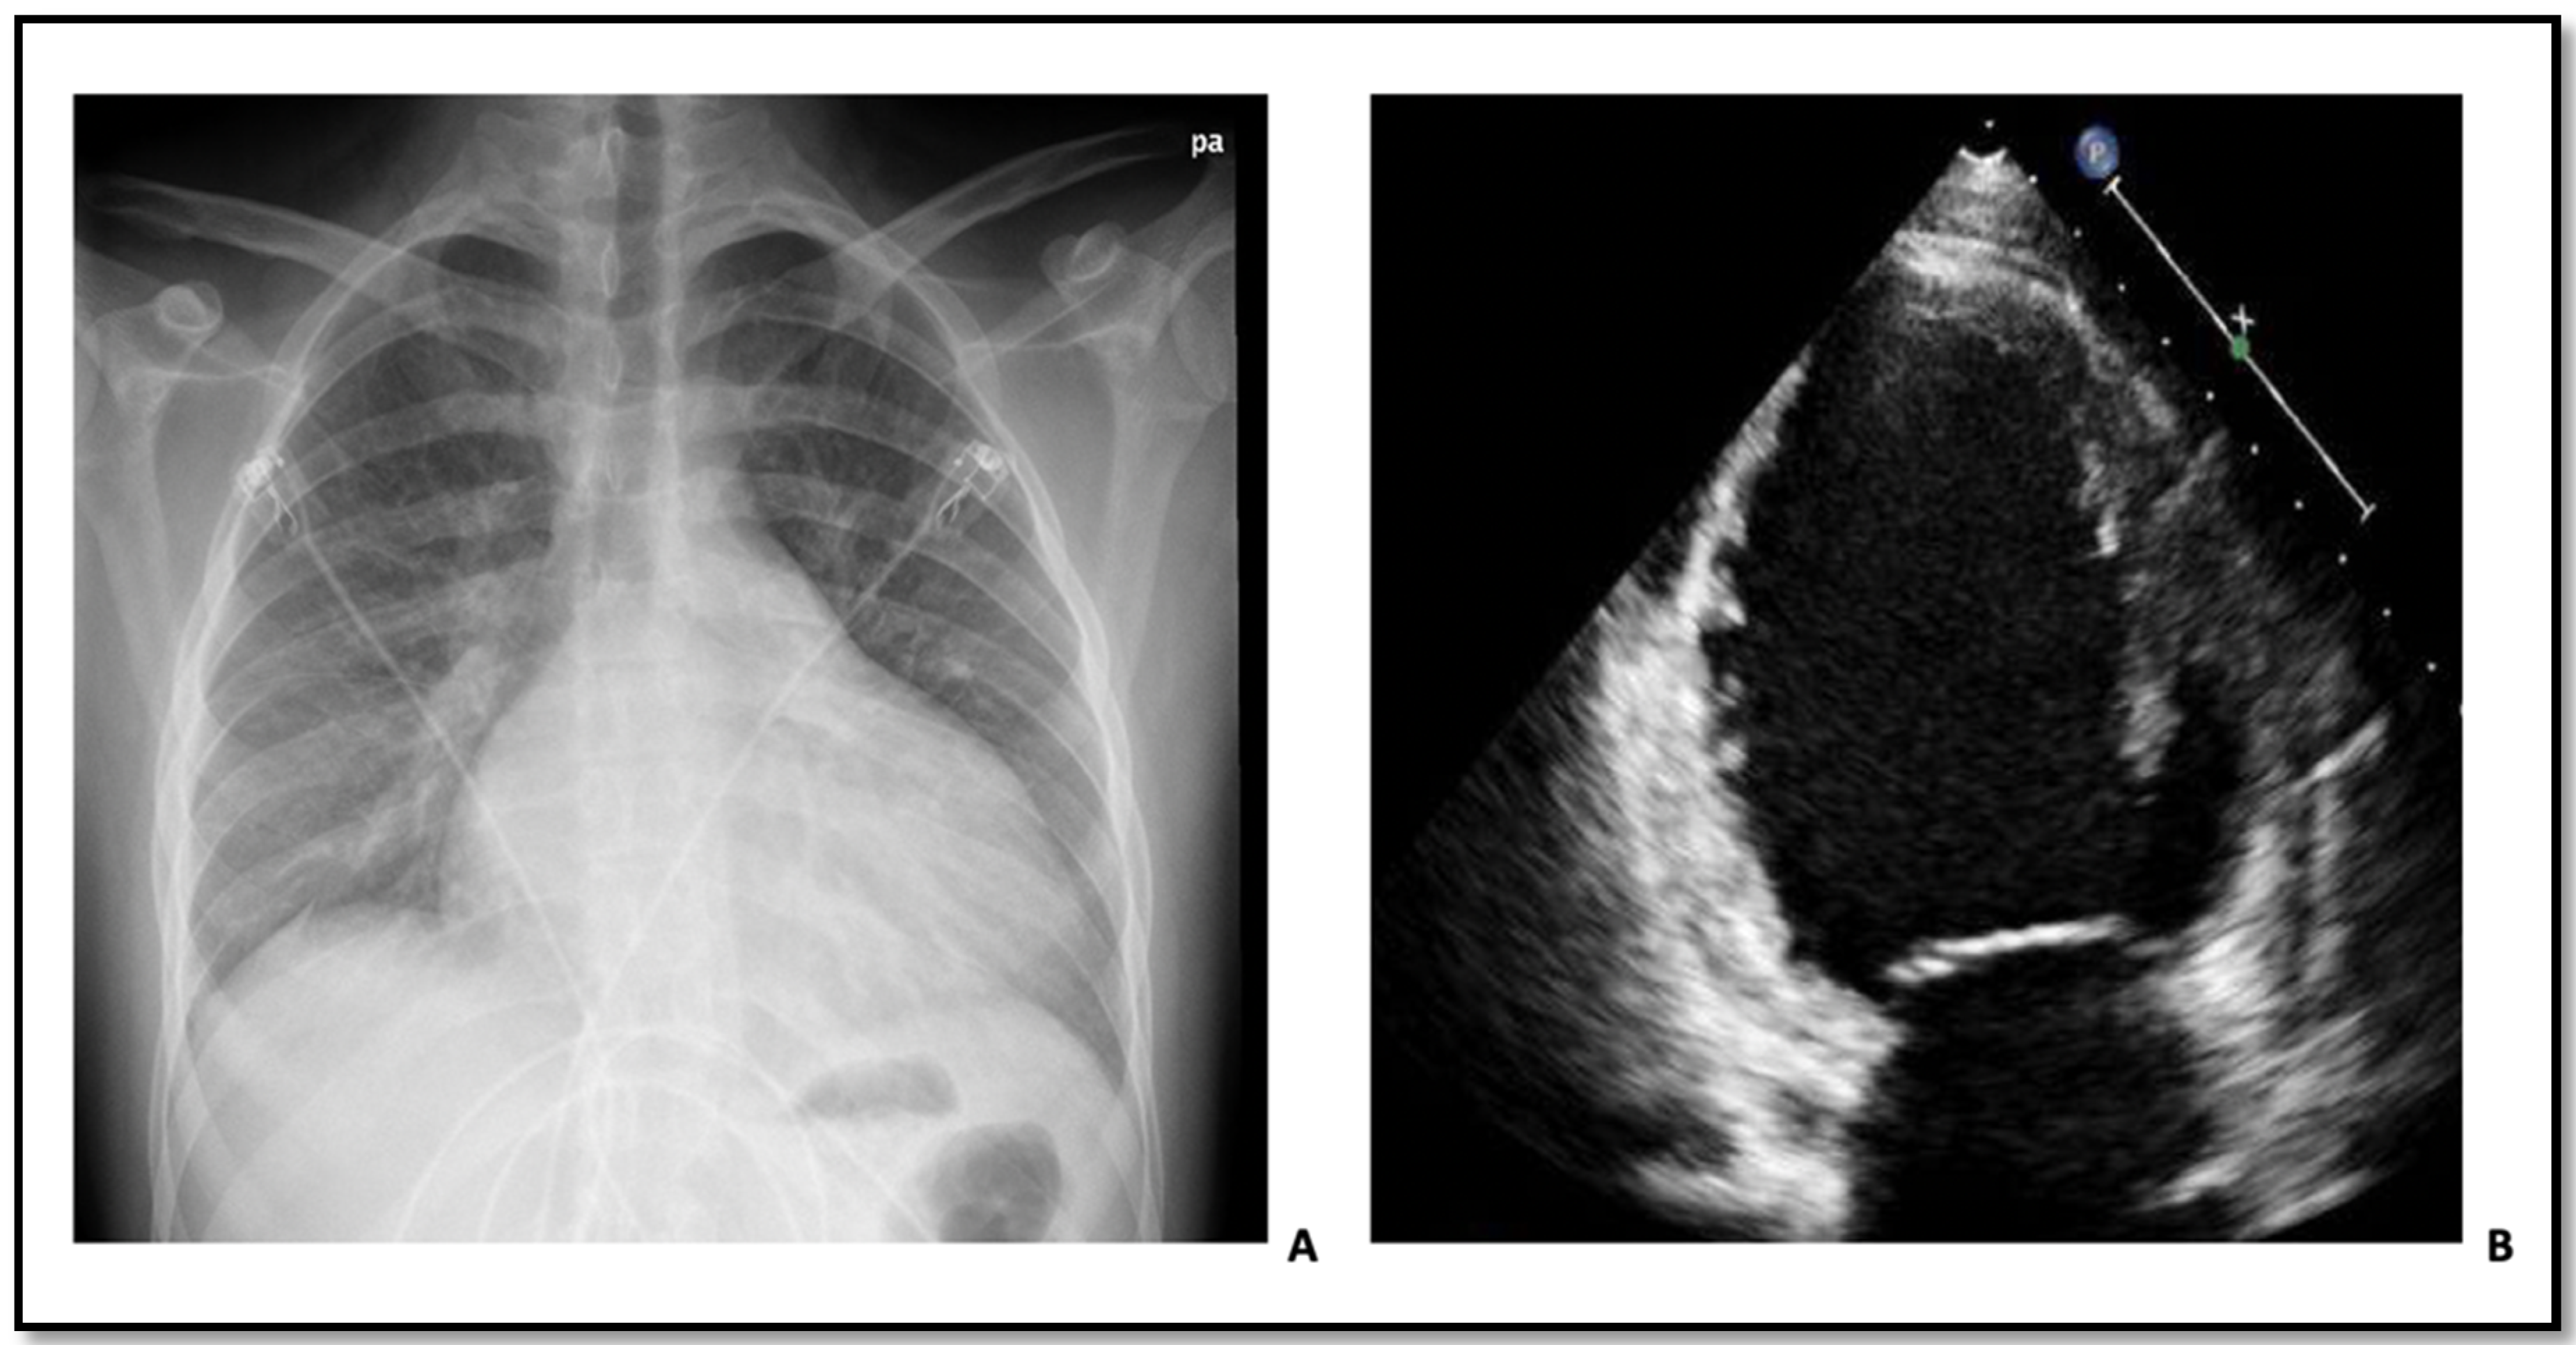

At the time of admission in 2011, the patient was hemodynamically stable (blood pressure 116/69, heart rate 100) and presented with a fever leading to initiation of antibiotic treatment due to suspicion of pneumonia. Routine blood testing including cardiac troponins, hematological, and kidney biomarkers were unremarkable. However, an ECG showed intraventricular conduction defect with a QRS-duration of 150 ms (Figure 2). A chest radiograph revealed cardiomegaly (Figure 3A). Subsequently, an echocardiography demonstrated severe left ventricular (LV) dilation with an end-diastolic diameter of 82 mm (indexed 41 mm/m2) and a LV ejection fraction (EF) of 10% (Figure 3B). These findings led to the initiation of anti-congestive medical treatment and later implantation of a cardiac resynchronization therapy-defibrillator. Further diagnostic work-up included genetic screening, right heart catheterization, and coronary angiography. The right heart catheterization showed a reduced cardiac index (1.8 L/min/m²) and elevated cardiac chamber filling pressures (right atrial pressure of 12 mmHg, mean pulmonary artery pressure of 47 mmHg, and wedge pressure of 31 mmHg). The coronary angiogram was normal, and the myocardial biopsy showed histologic features consistent with dilated cardiomyopathy with severely hypertrophic cardiomyocytes (Figure 4A–C).

Figure 3.

(A) Chest radiograph of patient 1 at admission time showing cardiomegaly. (B) Echocardiography of patient 1 at admission time showing severe left ventricular dilation.